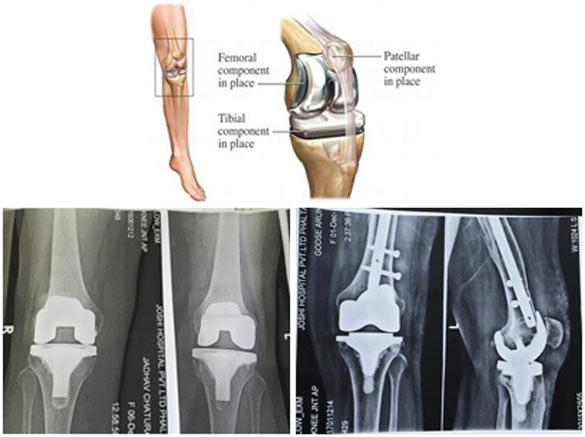

Knee Replacement

Knee replacement (knee arthroplasty) is a surgical procedure performed to replace damaged or worn knee joint surfaces with artificial components made of metal and plastic.

The surgery may be performed as a total knee replacement or partial replacement depending on the severity of joint damage. It is commonly recommended for osteoarthritis, rheumatoid arthritis and other degenerative knee conditions.